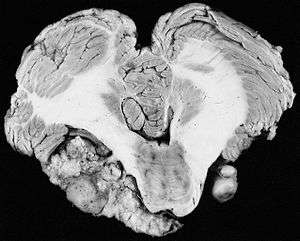

Acoustic neuromas (ARs), the common term for vestibular schwannomas, are neither 'acoustic' nor neuromas, since they do not arise from nerve tissue itself - ARs develop from an over production of non-neuronal glial (Schwann) cells that support and protect the vestibular (balance) portion of the vestibulocochlear nerve (cranial nerve VIII). ARs are slow-growing local, benign and non-invasive. Progression to malignancy in this kind of tumor is rare. They normally develop gradually over a period of years, expanding at their site of origin roughly 1–2 mm each year; however, up to 50% of such tumors do not grow at all, at least for many years after diagnosis. Tumor growth may be erratic, alternating between periods of relative dormancy or very slow growth and rapid growth. Tumors are typically described as small (less than 1.5 cm), medium (1.5 cm to 2.5 cm), large (2.5 cm to 4 cm),[9] or giant (greater than 4 cm). Tumors are described by a combination of their location and size. An intracanalicular tumor is small and in the internal auditory canal. A cisternal tumor extends outside the auditory canal. A compressive tumor infringes upon the cerebellum or brainstem. Very large tumors may obstruct cerebrospinal fluid drainage.

The tumor may develop within the auditory canal, where the vestibulocochlear nerve which supplies the inner ear penetrates the skull (intracanalicular neuroma) or outside the canal (extra-canalicular neuroma). The vestibulocochlear nerve has two components, the auditory and vestibular portions. Most schwannomas start out as intracanalicular, and growth compresses the nerve against the bony canal, so the first symptoms of the tumor are unilateral sensorineural hearing loss or distubances in balance. It may also compress the labyrinthine artery (main artery supplying the vestibular apparatus and cochlea of the inner ear) which passes through the auditory canal, resulting in ischemia or infarction ('heart attack' of the ear, resulting in death of the supplied tissue).

As intracanalicular tumors grow, they tend to expand into the cerebellopontine angle (CPA), leading to their characteristic "ice-cream-cone like" appearance on a radiograph. When the tumor expands extracanalicularly, the growth rate often increases, since it is no longer confined by the bony auditory canal. As the schwannoma expands into the CPA, it may infringe on cranial nerve V (controls facial sensation, chewing and swallowing) and cranial nerve VII (controls facial expression and taste). Cranial nerve VIII, along with these two nerves, also passes through the CPA, so more serious or complete hearing loss and episodes of vertigo may occur as the tumor infringes on it there.

When a schwannoma becomes large, it can displace normal brain tissue. The brain is not invaded by the tumor, but the tumor pushes the brain as it enlarges. Vital functions to sustain life can be threatened when large tumors cause severe pressure on the brainstem and cerebellum.